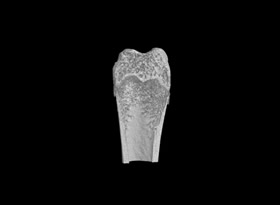

使用MicroCT可以詳細了解牙根管的三維形態(tài),測量根管的高度、體積、截面積、管壁厚度等。

1骨組織樣本掃描。

2提供2D圖、3D圖和相關參數(shù)的分析數(shù)據(jù)(骨密度BMD 單獨收費)。